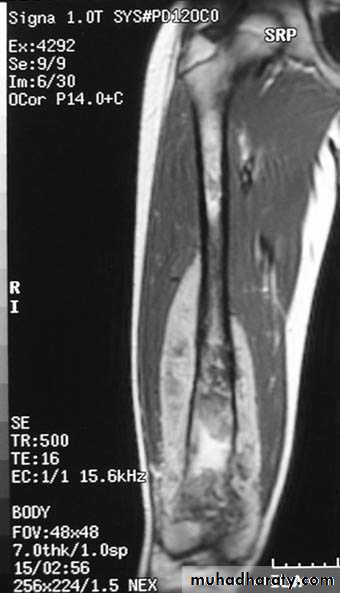

V.MRI (magnetic resonance imaging in bone disease ):

.demonstrate disc herniation and spinal cord or nerve root compression. to diagnose bone metastasis

.show extent of primary bone tumor & demonstrate myloma & lymphoma

. image soft tissue mass

. to diagnose osteomylitis & show any soft tissue abnormality

. to diagnose a vascular necrosis & other joint pathology .